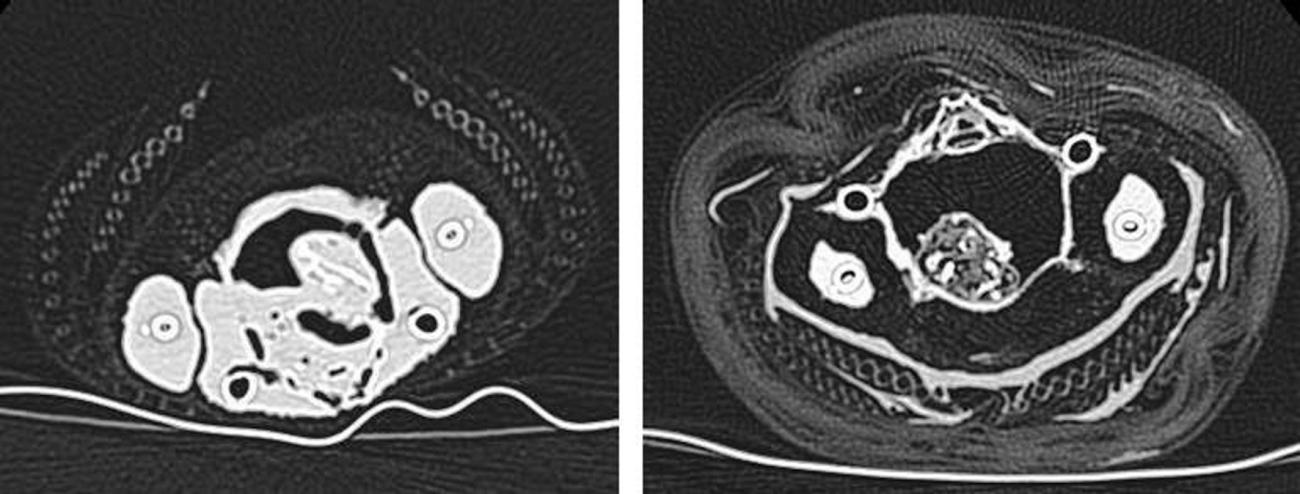

- The reduction in size of the visceral and muscle tissues; this was clearly noticeable using CT images from pre- and post-mummification (see Figure 13). It appears that desiccation is continuous, even after the anointment and wrapping methods were completed.